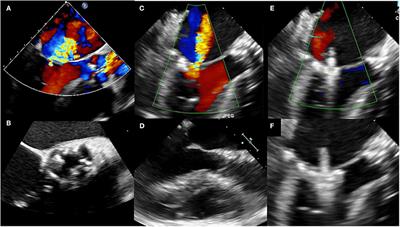

Aortic Valve Prolapse Echo